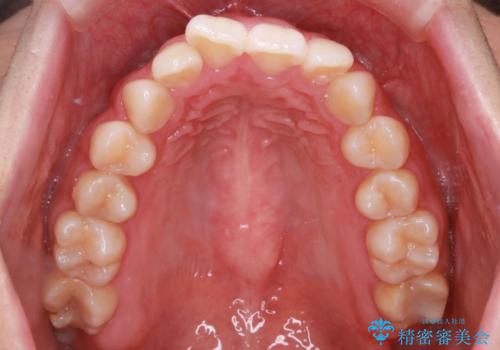

【インビザライン】前歯のねじれを治したい。

- 前歯の凸凹を主訴に来院されました。

スペースを作るために顎間ゴムを使用して、奥歯の遠心移動をおこない配列しました。

奥歯の遠心移動を行うことで、犬歯関係も良い状態に仕上げることができました。